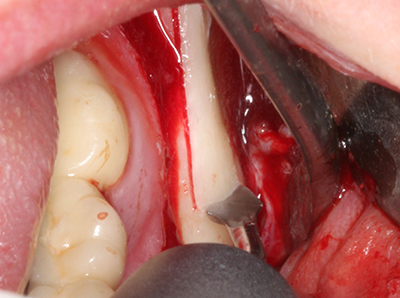

When surgical procedures are performed on bone in the immediate vicinity of sensitive structures such as blood vessels or nerves, rotary instruments pose a significant risk of iatrogenic injury. Piezoelectric devices can be helpful for preparation of bone covers and removal of hard tissue close to nerves, particularly for exposure of nerves after iatrogenic injury but also during nerve lateralization for resective and reconstructive procedures or implant placement (Fig. 17-20). Light contact between the piezotip and the nerve does not generally result in damage but proceeding incautiously with saw-like motions or attachments where a residual bone substrate remains may cause temporary or even permanent nerve damage. However, the risk of damage is considered to be substantially lower than when using saws or milling instruments (Pereira, Gealh et al. 2014).